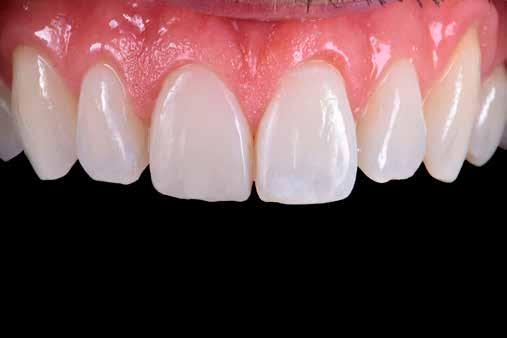

Egy 30 éves, negatív kórtörténettel rendelkező beteg azzal a kéréssel fordult hozzánk, hogy cseréljük ki az UR1 traumája után, 10 évvel korábban készült korábbi kompozit-helyreállítást.

A klinikai vizsgálat során az UR1 reagál a viabilitási tesztre, és az ugyanazon a napon készült röntgenfelvételen nem mutat periapikális elváltozásokat (1. ábra).

Az UR1 elszíneződött, és palatálisabb helyzetben van, mint az ellenoldali központi UL1 (2. ábra)

Az esztétikai elemzés a gingivális zenit aszimmetriáját mutatja az UR1 és az UL1 között. Parodontális szonda segítségével, plexusérzéstelenítés után, az IA

típusú funkcionális hám megváltozott passzív erupcióját igazoljuk Coslet és mtsai. osztályozása szerint (3. ábra)

A lehető legkonzervatívabb helyreállító kezelés elvégzése érdekében a páciensnél, figyelembe véve a megtartott fogelem korát és vitalitását, a tervezés és a diagnosztikai felviaszolás után a közvetlen kompozit-helyreállítás elvégzése mellett döntünk.

A kezelés napján, helyi plexusérzéstelenítést követően, az UR1-et kofferdámmal izoláljuk, kiterjesztve az izolációt az első premolárisokra (4. ábra)

Ezt követően eltávolítjuk a törött kompozt-helyreállítást, és az előkészített fogon rövid ferdére preparálást készítünk, majd az UR1 teljes felületén homokfúvást végzünk 27 μm-es alumínium-oxid porral (5. ábra)

A megváltozott passzív erupció korrigálása érdekében úgy döntöttünk, hogy a fog kiemelkedési profilját a vesztibuláris kidomborodás hangsúlyozásával és az ellenoldali elemmel való szimmetriára törekvéssel újra létrehozzuk. Erre a célra

egy előre megformázott fémmatricát használunk, amelyet két ékkel blokkolunk.

A matrica adaptálása után az adhéziós eljárásokat egy 3 lépéses etch&rinse rendszerrel végezzük. Minden egyes lépést 40 másodperces, UV-fénnyel történő polimerizálás követ (6. ábra)

A vesztibuláris kiemelkedési profilt zománcszínű kompozittal (a TOKUYAMA DENTAL ESTELITE ASTERIA WE termékével) állítjuk helyre (7. ábra).

A diagnosztikai felviaszolás szilikonindexének elkészítése után a palatinális falat zománcszínű kompozittal (a TOKUYAMA DENTAL ESTELITE ASTERIA WE termékével) helyreállítjuk (8. ábra)

Ezt követően helyreállítjuk a dentin anatómiáját a mamelonok reprodukálásával egy átlátszatlan dentinszínű kompozittal (a TOKUYAMA DENTAL ESTELITE SIGMA QUICK OA2 termékével); ez a szín alapvető fontosságú lesz a diszkromatikus elem színének korrigálásához is (9. ábra) Világoskék és fehér hatású árnyalatokat (a TOKUYAMA

DENTAL ESTELITE COLOR termékét) alkalmazunk az opá-

losság emulálásához az incizális területen (10. ábra)

A rétegezést egy zománcszín (a TOKUYAMA DENTAL ESTELITE ASTERIA WE terméke) használatával végezzük a vesztibulárisban, egyszeri hozzáadással. A vesztibuláris felületet háromdimenziós térfogatban modellezzük és vezéreljük annak érdekében, hogy a lehető legkevesebb végső kiigazítás legyen. Ezután 20 másodpercig polimerizáljuk, majd 40 másodpercig polimerizáljuk vesztibulárisan és palatinálisan, miután bevontuk őket gliceringéllel a kompozit hibrid rétegének elkerülése érdekében (11. ábra).

A finírozási és polírozási eljárásokat úgy végezzük, hogy megpróbáljuk emulálni az UL1 átmenő vonalait (12–13. ábra)

A pácienst 21 nap (14–15. ábrák) és 12 hónap (16. ábra) után ismét ellenőrizzük, hogy értékeljük az esztétikai eredményt a forma és a szín tekintetében.